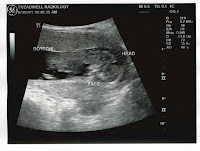

I actually have a pretty legitimate reason to be so tired and it's not laziness or working too much...

Yup! I'm pregnant! It was a bit of a surprise and not something we were really planning but we're pretty excited.

So I'm due September 20th and I've just ticked over to 13 weeks and the second trimester. I got to celebrate hitting 13 weeks this morning by throwing up. Lovely. So far though, that's only the second time and both times seem to have come after a busy day at work where I'd been quite tired. I've had nausea on and off the whole time, more so when I'm in the car (curse you motion sickness!) so I think I'm pretty lucky I've actually only barfed twice.

I actually have a pretty legitimate reason to be so tired and it's not laziness or working too much...

Yup! I'm pregnant! It was a bit of a surprise and not something we were really planning but we're pretty excited.

So I'm due September 20th and I've just ticked over to 13 weeks and the second trimester. I got to celebrate hitting 13 weeks this morning by throwing up. Lovely. So far though, that's only the second time and both times seem to have come after a busy day at work where I'd been quite tired. I've had nausea on and off the whole time, more so when I'm in the car (curse you motion sickness!) so I think I'm pretty lucky I've actually only barfed twice.